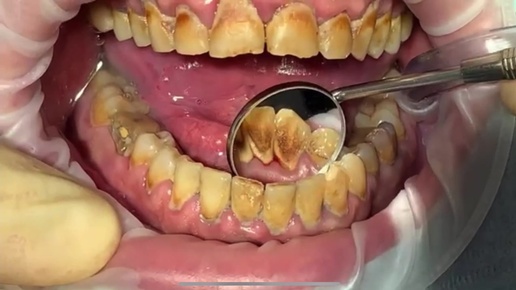

Ультразвуковая чистка зубов